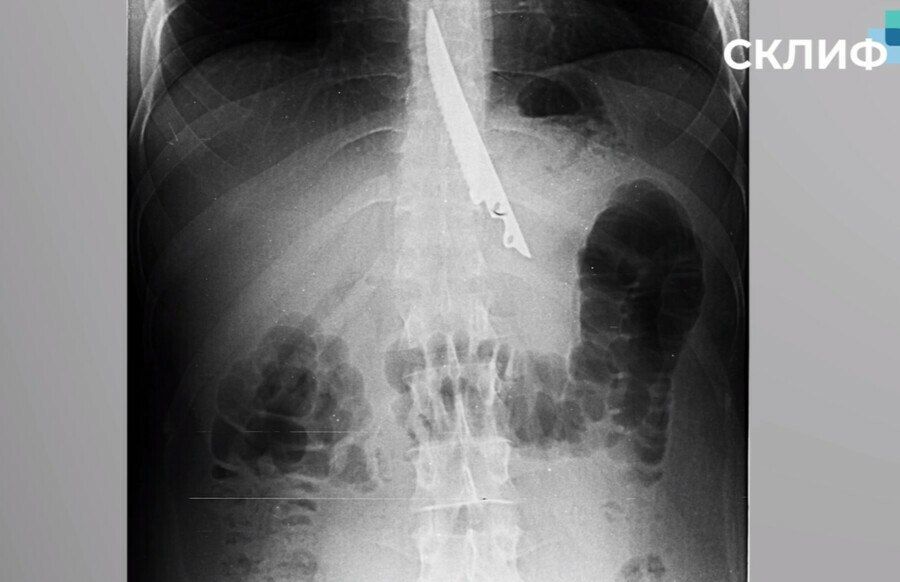

Москвич подавился мясом на пикнике. Чтобы протолкнуть застрявший кусок, друзья взяли 20-сантиметровый нож, но мужчина проглотил и его.Пострадавшего спасли врачи. Нож мужчина оставил им на память.Ты...